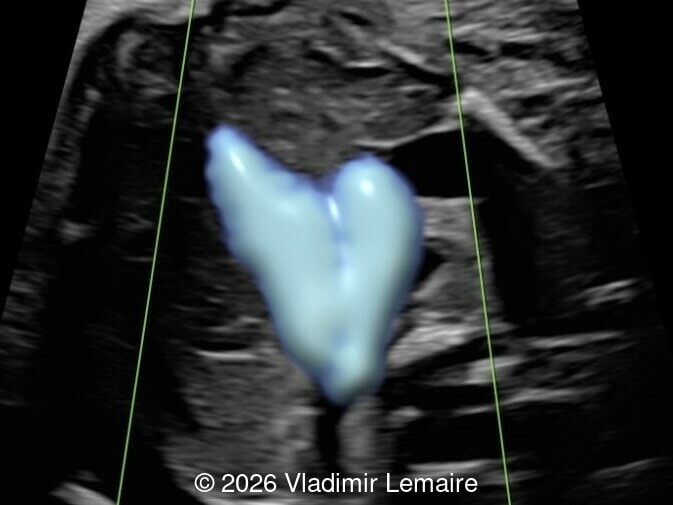

The three-vessel-trachea view with color Doppler.

Image 5 The three-vessel-trachea view with color Doppler.

Our imaging revealed enlargement of the fetal heart with dilation of the superior vena cava. On further evaluation, we identified an elongated anechoic cystic structure in the midline of the head, without mass effect on the surrounding structures. Color doppler demonstrated an arteriovenous fistula between the deep choroidal arteries and the embryonic median prosencephalic vein of Markowski. The vein of Galen aneurysmal malformation was likely the contributing factor to the cardiac enlargement. Cardiac function was, however, preserved and hydrops not present. Additional images are shown below.

On ultrasound, a VGAM appears as an elongated anechoic cystic structure in the middle of the head, often without mass effect on the surrounding structures. Color Doppler shows high-velocity flow in the lesion and can be used to identify the arteries feeding the vascular malformation. Pulsed-wave Doppler shows markedly turbulent flow. Additional key echocardiographic features include an enlarged heart with preserved systolic function, a dilated superior vena cava, and mild or moderate tricuspid regurgitation. Tricuspid regurgitation was not present in our case at the time of our evaluation.